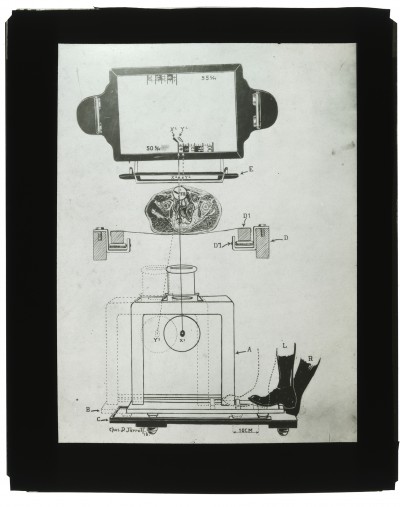

Dr. Edwin Ernst, an only child born to St. Louis residents Charles and Catherine Ernst, was a notable Roentgenologist, a physician who specializes in radiological work. Dr. Ernst studied at Washington University in St. Louis and later at Moravian College in Bethlehem, Pennsylvania earning his advanced degrees. For two years he served as a resident physician at the St. Louis Mullanphy Hospital before leaving to pursue a private practice. When the United States formally entered the war in 1917, Ernst left St. Louis to become chief radiologist at Base Hospital 21. He was discharged honorably in 1919 with the citation of Major. His collection consist of x-ray images taken at Base Hospital 21 as well as drawings of radiological equipment and photographs.